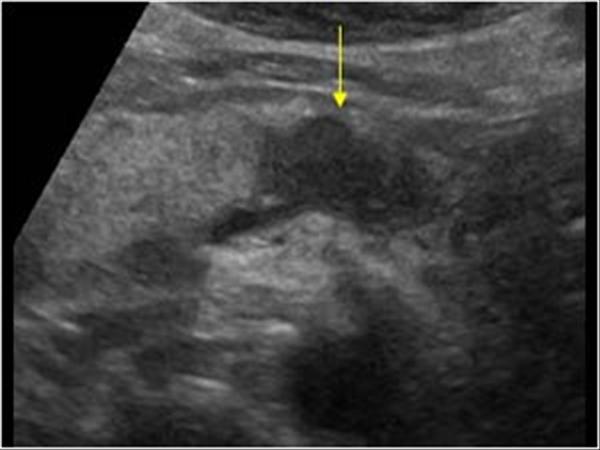

U tụy

» Thông tin: Nữ giới – 57 tuổi.

» Lâm sàng: Sút cân.